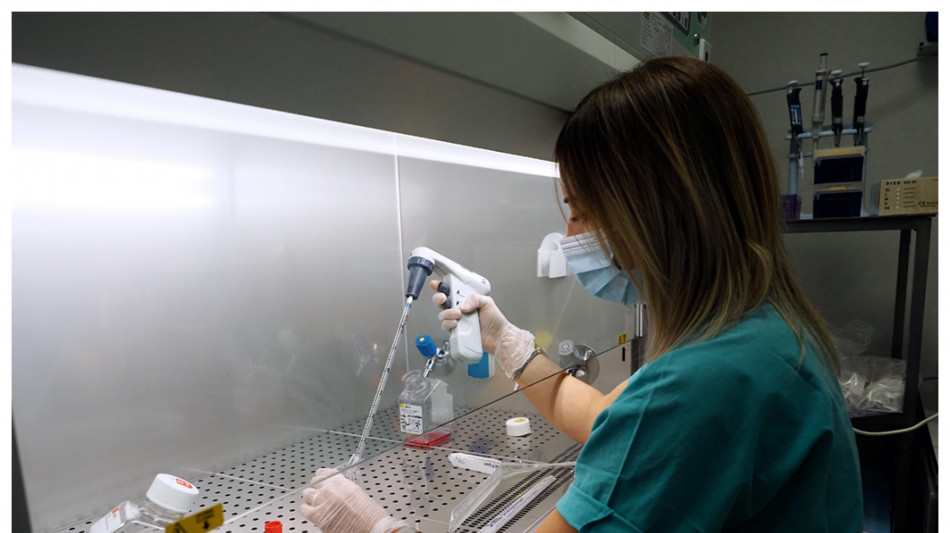

Pronta l'armatura per i superbatteri dell'industria farmaceutica

Li rende più efficienti e ne allunga la vita

Sonde fluorescenti ascoltano le cellule, utili a future terapie

Controllano lo scambio di messaggi molecolari al loro interno